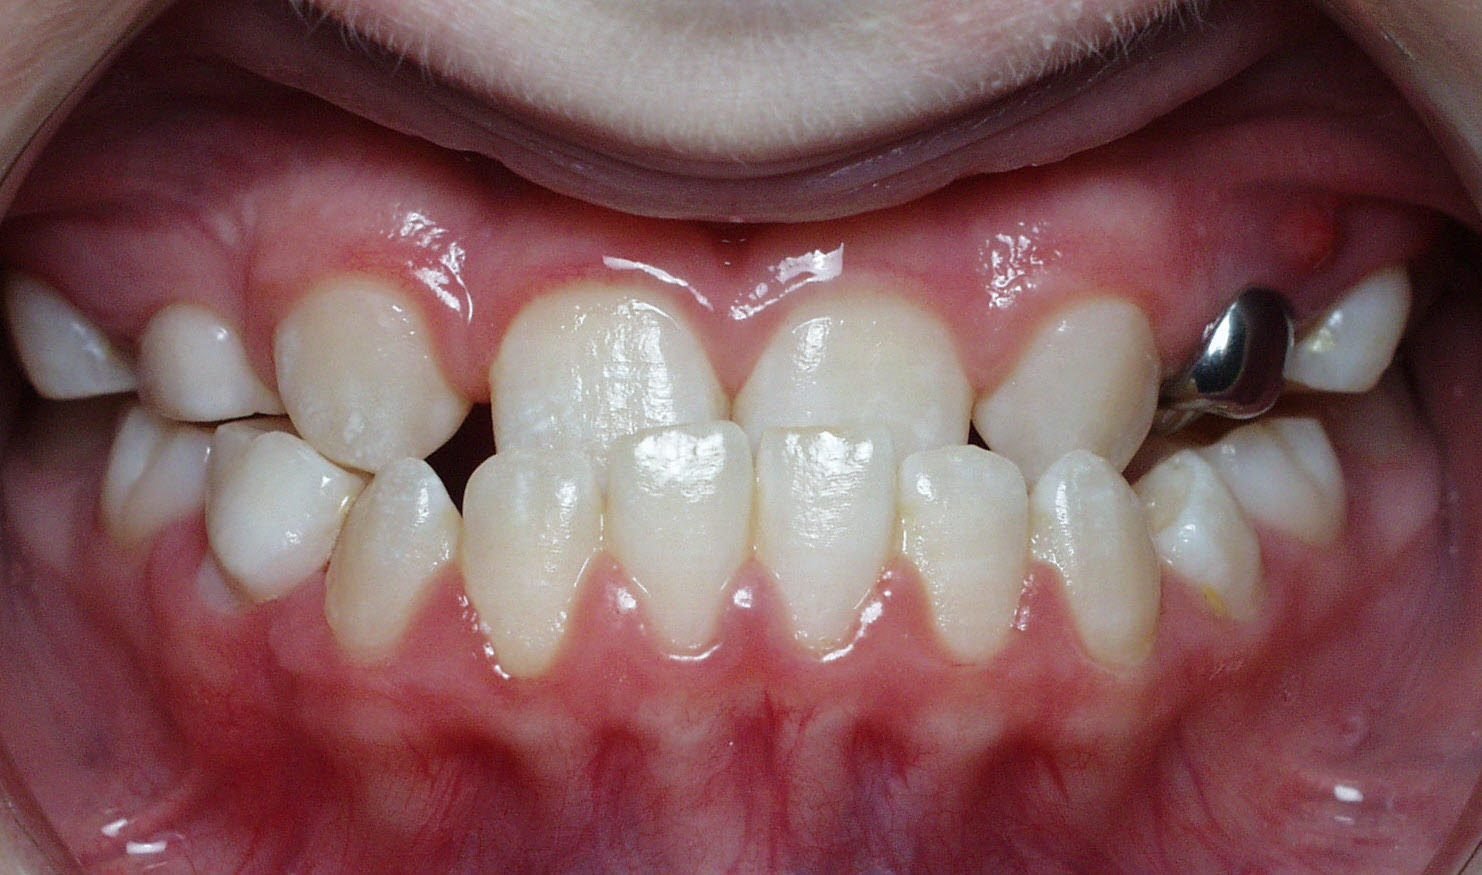

Malocclusion

Clinical Presentation: Misaligned teeth, difficulty chewing, jaw pain, and TMJ discomfort.

Zebris Findings: Abnormal or uneven jaw movements, discrepancies in occlusal contacts, and uneven load distribution across the TMJ.

Crossbite

Clinical Presentation: One or more teeth bite on the inside of the opposing teeth.

Zebris Findings: Lateral discrepancies in jaw movement, uneven load distribution, and compensatory asymmetrical movements.